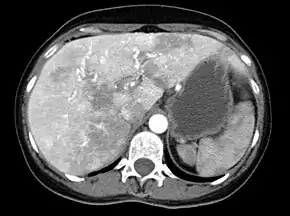

CT-scan of vascular malformations in the liver in a patient with hereditary hemorrhagic telangiectasia causing an inhomogeneous perfusion pattern.

Liver AVMs may be suspected because of abnormal liver function tests in the blood, because the symptoms of heart failure develop, or because of jaundice or other symptoms of liver dysfunction. The most reliable initial screening test is Doppler ultrasonography of the liver; this has a very high sensitivity for identifying vascular lesions in the liver. If necessary, contrast-enhanced CT may be used to further characterize AVMs.[3][4][8] It is extremely common to find incidental nodules on liver scans, most commonly due to focal nodular hyperplasia (FNH), as these are a hundredfold times more common in HHT compared to the general population. FNH is regarded as harmless. Generally, tumor markers and additional imaging modalities are used to differentiate between FNH and malignant tumors of the liver. Liver biopsy is discouraged in people with HHT as the risk of hemorrhage from liver AVMs may be significant.[8][9] Liver scans may be useful if someone is suspected of HHT, but does not meet the criteria (see below) unless liver lesions can be demonstrated.[9]